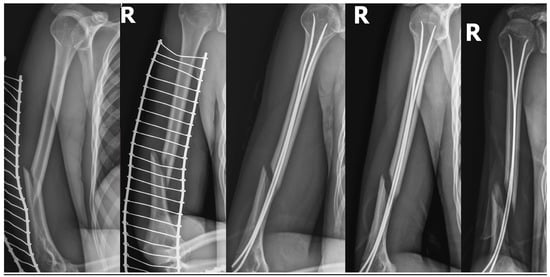

| 1. | Boy/8.6 years | Close/ Simple spiral/Middle thirds AO 12A1b | Low-energy trauma | Neuropraxia | CRIF/FIN expectant observation | spontaneous recovery after 2.5 months | 30 months | |

| 2. | Girl/16.3 years | Close/ Simple oblique/Distal thirds AO 12A2c | High-energy trauma/fall from 8 m | Lungs contusion. Bilateral pneumothorax. Fracture of the sacrum. | Neurotmesis | ORIF/titan plate + nerve reconstruction with a sural nerve cable graft. | recovery after 7.5 months | 20 months |

| 3. | Boy/13.5 years | Close/ Simple transverse/Distal thirds AO 12A3c | Low-energy trauma | Entrapment between bone fragments | ORIF/titan plate + nerve exploration 23 days after injury—2 days after nerve palsy. | recovery after 3.3 months | 8 months | |

| 4. | Boy/17.2 years | Open GA 1/ Intact wedge/Distal thirds AO 12B2c | High-energy trauma/fall from 6 m | Right scapula fracture. Multifragmentary fracture of the left distal forearm. Stable Th8 compression fracture. Left lateral mass fracture of the sacrum. Right iliac wing fracture. Right pubic bone fracture. Lungs contusion with a minor bilateral pneumothorax. | Entrapment between bone fragments | CRIF/external fixator ORIF/titan plate + nerve exploration 16 days after injury | recovery after 4.6 months | 16 months |

| 5. | Boy/12.3 years | Open GA 2/Simple transverse/Distal thirds AO 12A3c | High-energy trauma/hit by a car | Numerous wounds and bruises. Lung contusion. Right distal radius fracture. | Neurotmesis | ORIF/FIN with no nerve exploration due to wound contamination; implant removal + nerve reconstruction with a sural nerve cable graft 4.5 months after injury. | recovery 5.5 months after nerve reconstruction/15.5 months after injury! | 18 months |

| 6. | Boy/17.5 years | Close/ Simple spiral/Distal thirds AO 12A1c | Low-energy trauma | Stretching over the bone fragments | CRIF/FIN ORIF/titan plate + nerve exploration 56 days after injury—slowly progressive palsy. | recovery after 2 months | 5 months |